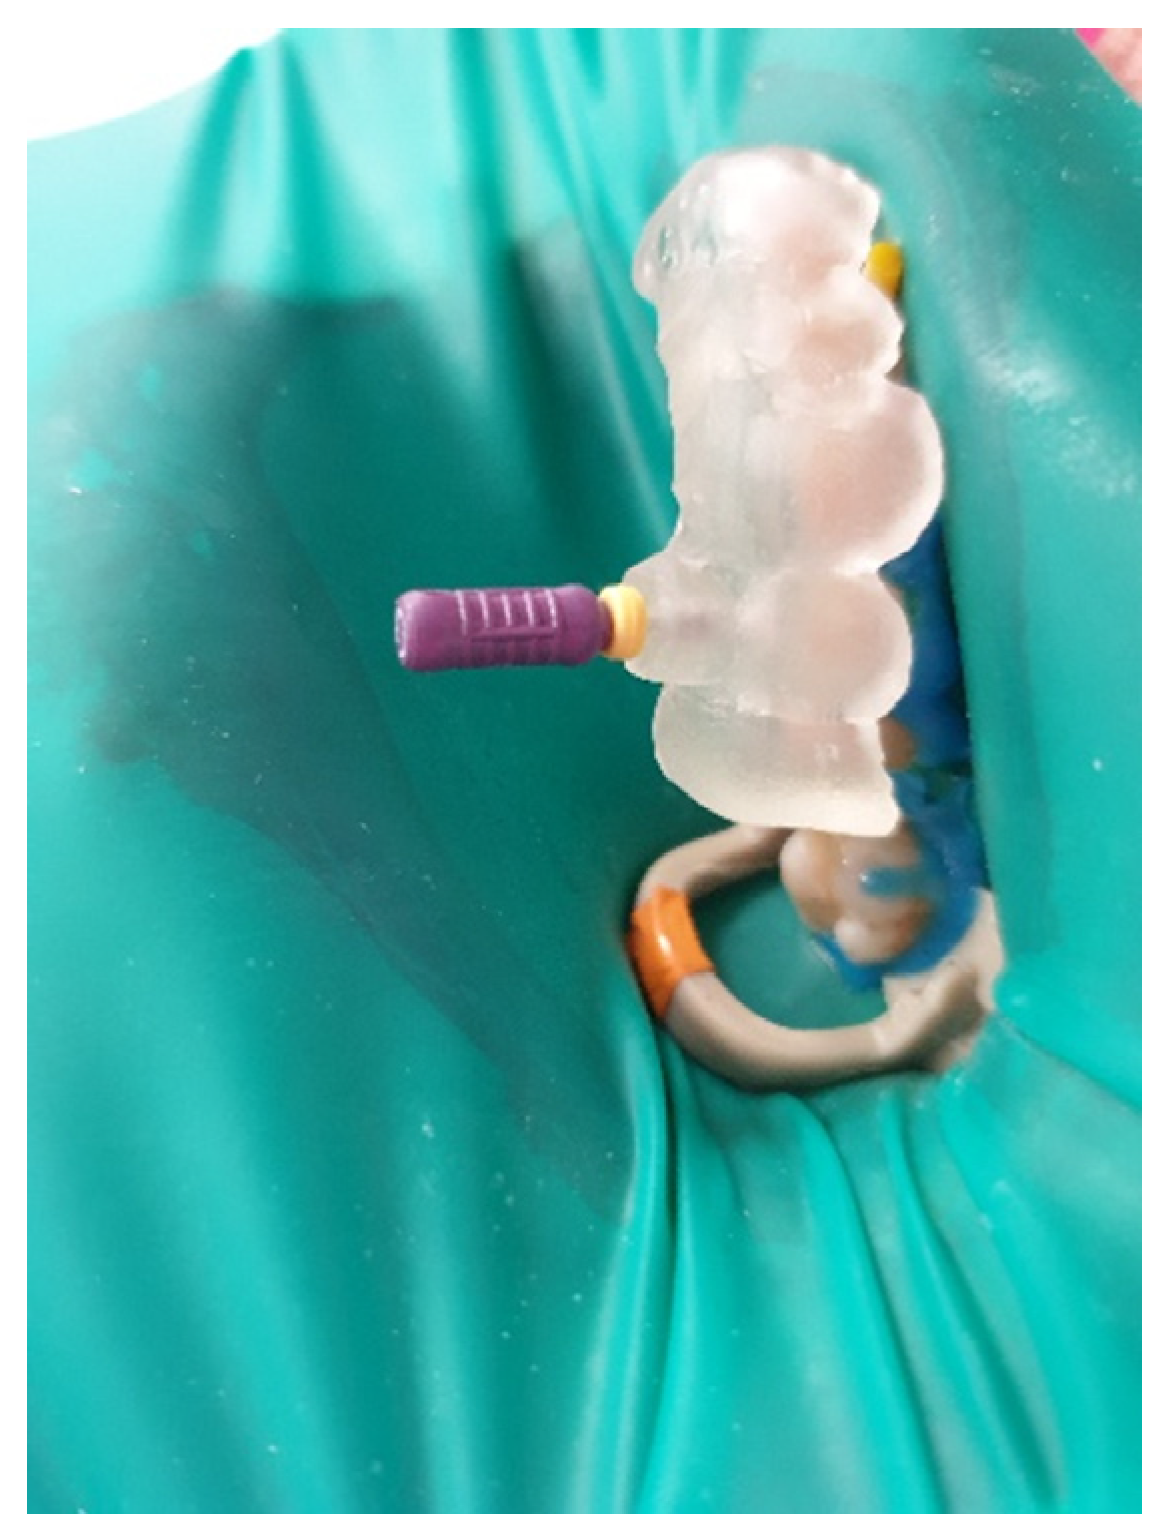

The buccal canal was cautiously negotiated through the guide with a size 10 file (C-Pilot #10) instead of rotated burs (Figure 22). The root canal orifice was reached at a length of 17 mm from the top of the guide sleeve. The time needed to localize the canal path in this case was approximately 15 min. The file was taken to the working length and a conventional root canal treatment followed (Figure 23).

Figure 22. Image presenting endodontic guide placed on patient’s teeth. Root canal was negotiated with a C-Pilot file.